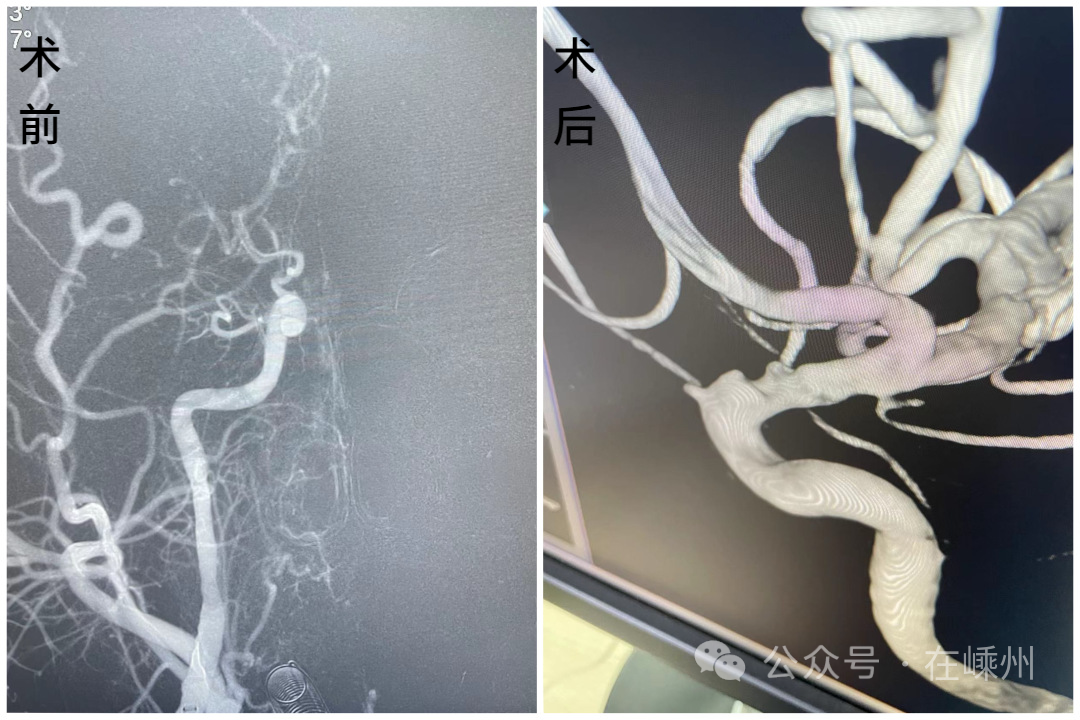

年僅33歲的徐先生是一位資深煙民,平時工作忙碌的他,喜歡熬夜打游戲來緩解工作壓力。然而在不久前的某天晚上,他突然出現(xiàn)口角歪斜、言語含糊、反應遲鈍、不能站立行走等情況,被家人送到市中醫(yī)院急診科,經(jīng)過檢查確診為右側(cè)頸內(nèi)動脈閉塞、腦栓塞。

對于這類患者來說,唯一救治的辦法就是急診開通血管。為挽救更多的腦細胞,最大限度減少對患者日后生活的影響,中醫(yī)院當即開通救治綠色通道,在最短的時間內(nèi)為徐先生進行了手術(shù)。這次經(jīng)歷,對徐先生來說,是一次生死劫,更是一次健康的警鐘。